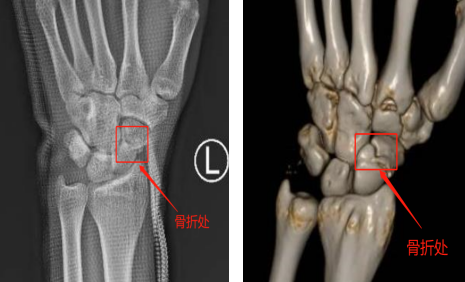

爱运动的小刘在和朋友打球时不慎与队友相撞摔倒,摔倒时他左手手掌惯性撑地,导致左腕疼痛剧烈,无法进行正常活动。手外科唐医生接诊后通过X片及三维重建均显示小刘为左腕舟状骨骨折。

术前X片(左图)术前三维重建(右图)